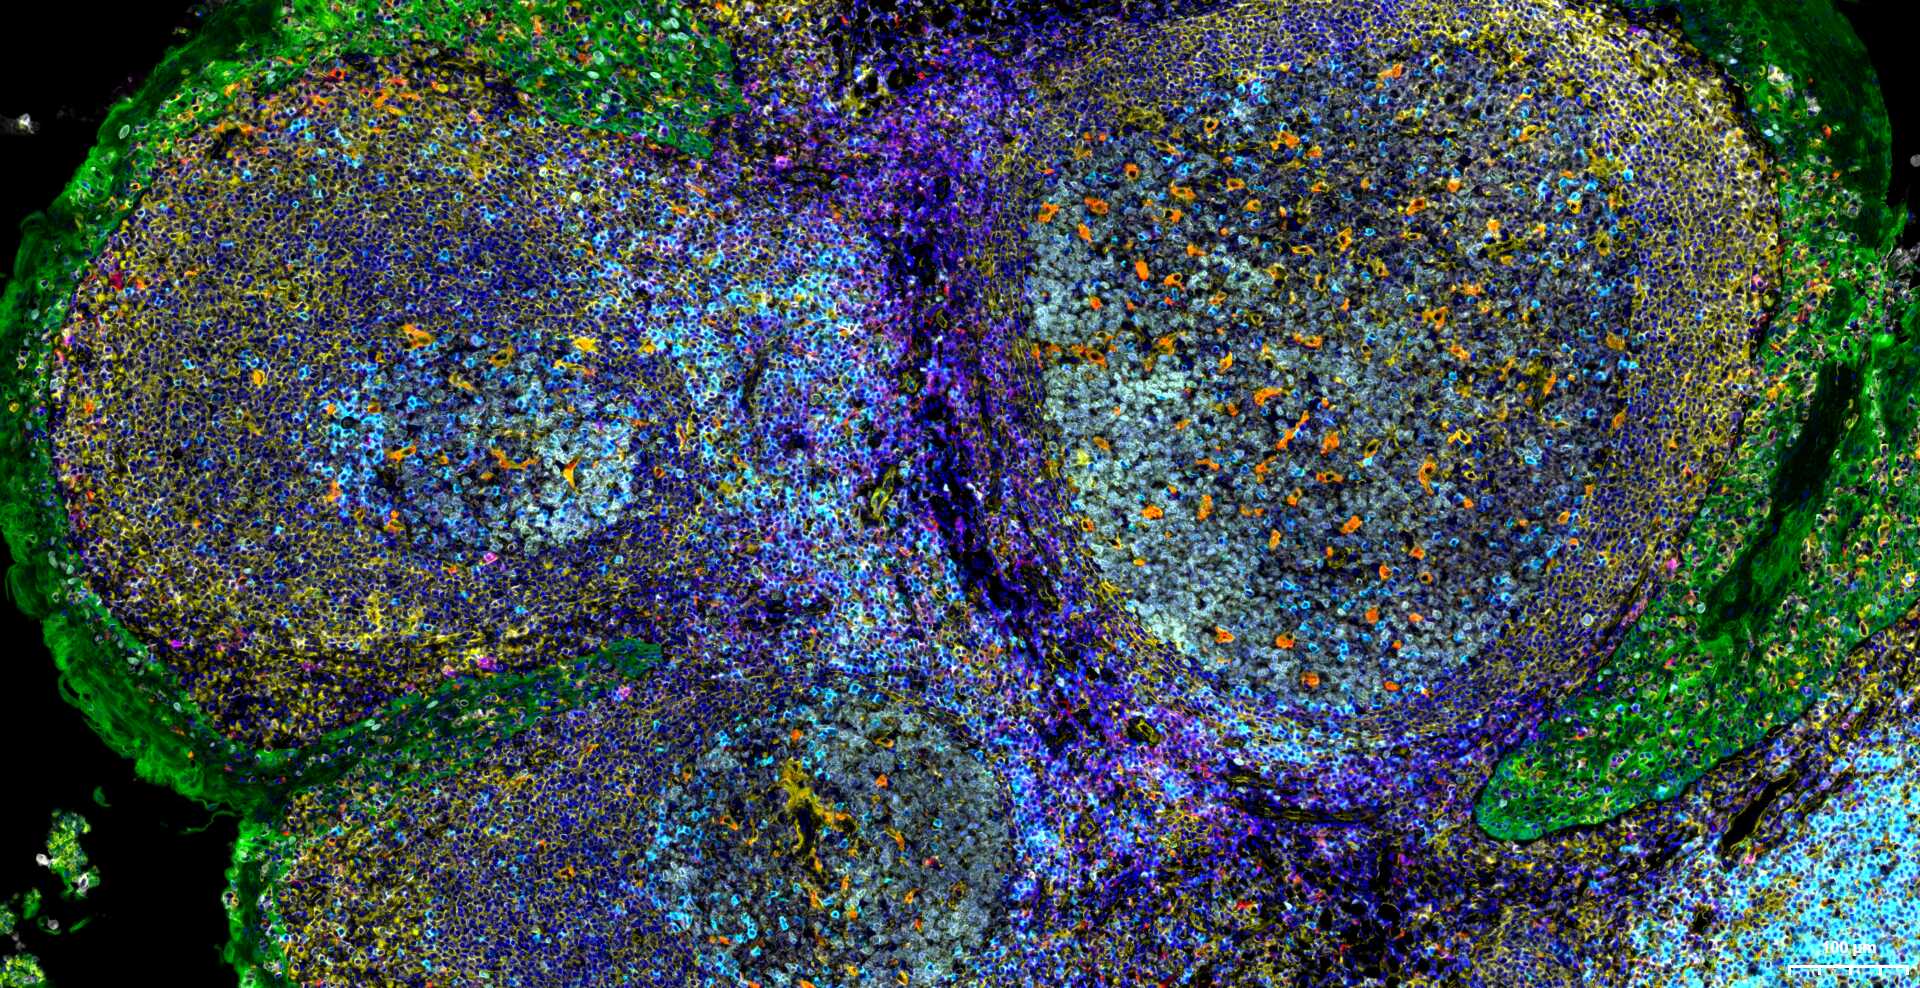

Immunology > Adaptive Immunity > Regulatory T Cells

Immunology > Adaptive Immunity > T Cells > CD

Stem Cells > Hematopoietic Progenitors > Lymphoid > T Lymphocytic Lineage

Stem Cells > Hematopoietic Progenitors > Myeloid > Dendritic Cell Lineage

Stem Cells > Hematopoietic Progenitors > Myeloid > Monocytic Lineage

| mIHC | Human | 1:100-500 |